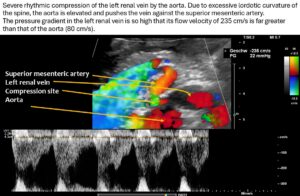

As a result of the pronounced lordosis and the associated ventral displacement of the aorta, the left renal vein is also severely compressed.

The narrowest point is located at the arcuate origin of the right renal artery. The lumen of the renal vein is barely recognizable. As a result, there is a significant acceleration of flow from 14 cm/s to the left of the aorta to 235 cm/s at the narrow point. This is a severe hemodynamically significant outflow obstruction of the left kidney, often somewhat misleadingly referred to as nutcracker syndrome. This constellation is responsible for the pain radiating from the epigastrium to the left hypochondrium. As the stomach fills, the compression exerted by the greater curvature on the tense renal vein intensifies the discomfort in the epigastrium. The left renal vein runs relatively far cranially.